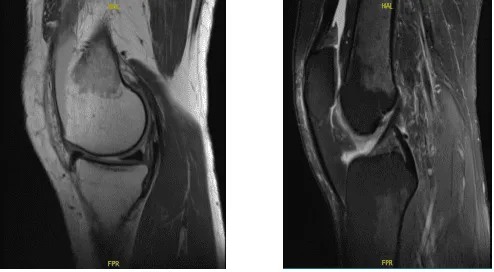

Un paciente de 47 años presenta dolor en la rodilla izquierda que comenzó hace una semana. Trabaja como enfermera de hemodiálisis en SBU y está de baja debido a este dolor. Ella tiene dolor, hinchazón, deformaciones y la inflamación ha disminuido. Intentó una gestión conservadora pero no obtuvo ningún beneficio. El médico le aconsejó hacerle una resonancia magnética.

El médico realizó una resonancia magnética, la revisó y la discutió; los hallazgos indicaban ligamentos colaterales: El ligamento colateral medial está intacto. El ligamento colateral lateral, el tendón del bíceps femoral, la banda iliotibial y el tendón poplíteo están intactos.

Ligamentos cruzados: Los ligamentos cruzados anterior y posterior están intactos. Meniscos: El menisco medial está intacto. El menisco lateral está intacto. El cartílago: Hay un defecto condral de 9 x 6 mm de grosor completo en la porción media del cóndilo femoral medial.

Las superficies condrales en el compartimento lateral están intactas. Existe una zona focal de fisuración condral y pérdida de cartílago de grosor parcial en la troclea central. Hueso: Las estructuras óseas visualizadas muestran una intensidad normal de la médula ósea y la señal cortical, sin evidencia de fractura, lesión ósea trabecular o luxación.

No se identifican lesiones óseas. El mecanismo extensor: Los tendones del cuádriceps y la rótula están normales. Articulación: Derrame grande en la articulación de la rodilla. Por lo demás, los tejidos blandos son normales. Las estructuras neurovasculares muestran un curso normal.

Presenta una impresión de un defecto condral de 9 x 6 mm de grosor completo en la porción media del cóndilo femoral medial. Área focal de fisuración condral y pérdida de cartílago de espesor parcial en la troclea central. Menisco medial y lateral intacto.

MRI-3T Rodilla izquierda sin contraste